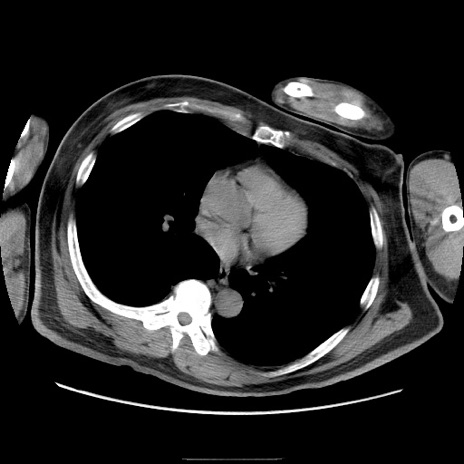

症例22(横断像)

【症例】50歳代男性

【主訴】腹痛

【現病歴】AVMからの被殻出血のため回復期リハ病棟入院中。 本日午後3時頃急に下腹部痛が出現した。

【既往歴】AVM、被殻出血、虫垂炎、高血圧

【身体所見】意識晴明、左半身不全麻痺、会話の理解は良好、36.5°C、腹部:膨隆、全体に板状硬、下腹部正中に圧痛点あり、反跳痛-、筋性防御不明、右下腹部にope scar

【データ】WBC 9400、CRP 0.06